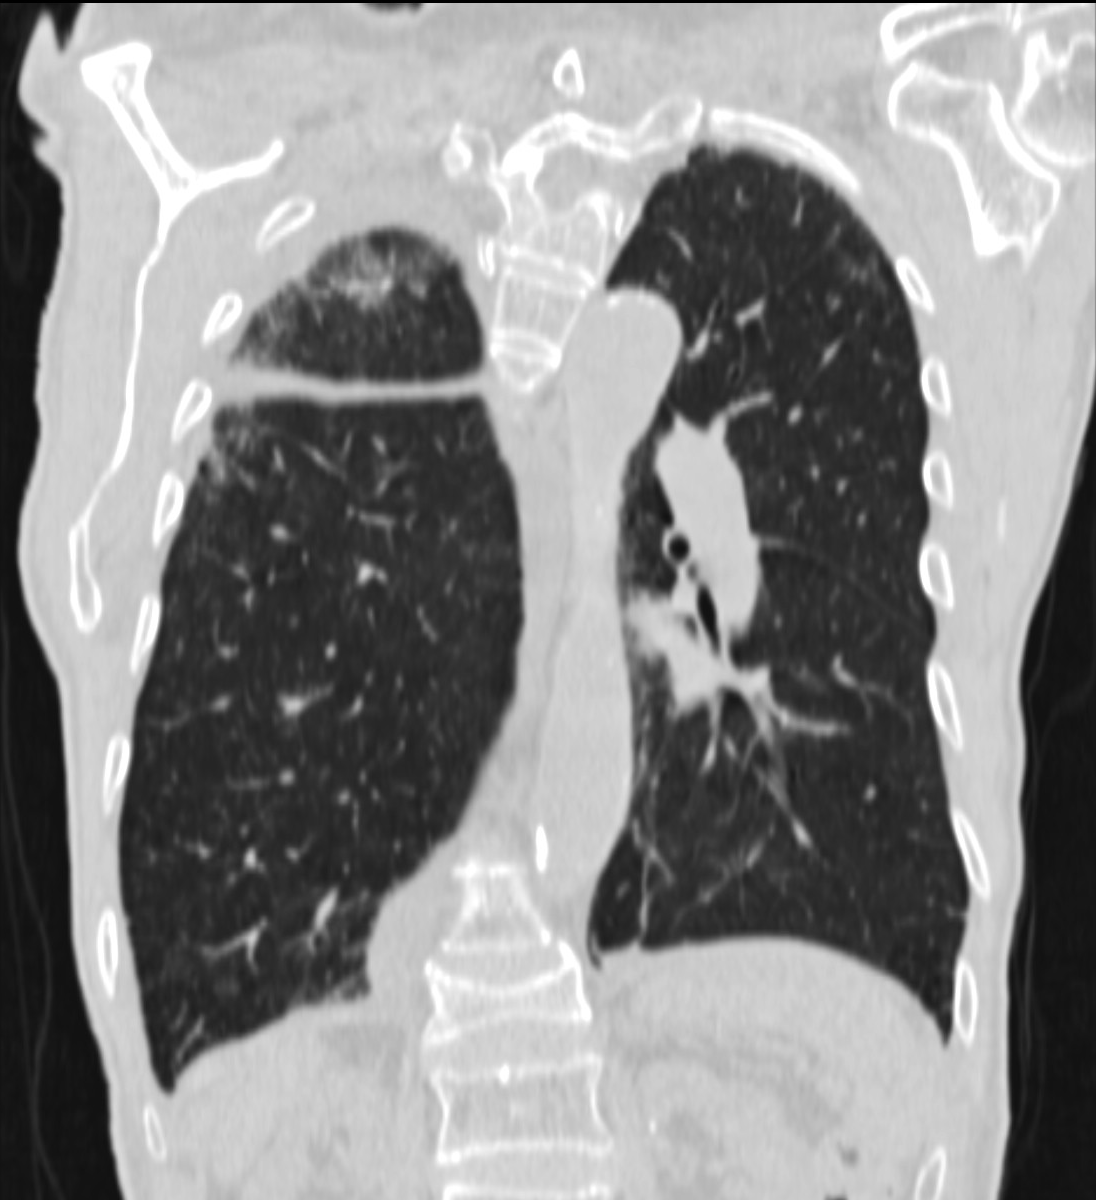

22. Central lung tumor with mediastinal lymphadenopathy. CT coronal and sagittal reconstructions.

70 year old man, COPD, hoarse. Right hilar mass, bronchoscopy was negative.

The larynx is rotated to the right, no motion of the right side of the larynx can be observed, swollen left plica ventricularis area.

CT: 13x11 mm large nodular mass in the left 10th segment. Bilateral hilar lymphadenomegaly with central hypodensity. A 34x21 mm large lymph node conglomeration can be observed in subcarinal location (peripheral contrast enhancement). Lymphadenopathy in the aortopulmonary window (15 mm large), and a 26 mm large lymph node can be observed in paraaortic location above the trachea bifurcation which has an esophagus-compressing effect. In the superior chest aperture there is a 38x28 large fused lymph node conglomerate which causes the left shift of the esophagus and trachea.